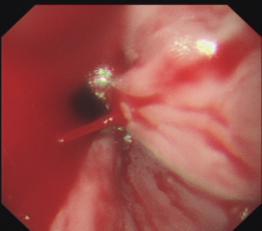

3. 食管曲張靜脈硬化劑注射、套扎術(shù)及胃底靜脈曲張組織膠注射栓塞術(shù):在全市首先開展,處領(lǐng)先水平;

食管曲張靜脈出血套扎術(shù)